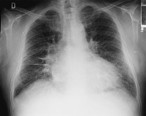

Esta enfermedad es el paradigma de la insuficiencia cardíaca con función sistólica deprimida, con todos los signos y síntomas propios de esa situación. ☤

- Síntomas de congestión pulmonar:

- Disnea de esfuerzo

- Ortopnea

- Tos nocturna

- Disnea paroxística nocturna

- Síntomas de congestión sistémica:

- Retención de líquidos (si predomina la IC derecha)

- Síntomas de bajo gasto cardíaco:

- Astenia, fatigabilidad

- Oliguria

Las embolias se producen con más frecuencia que en otras causas de insuficiencia cardíaca, probablemente en relación con la gran dilatación de las cámaras cardíacas.

Exploración física

Puede presentarse debilidad y desplazamiento hacia abajo y hacia afuera del impulso apical, así como tercer y/o cuarto ruidos, pulso alternante, datos de hipertensión pulmonar y fallo derecho en casos avanzados.

Frecuentemente existe soplo sistólico debido a insuficiencia mitral por dilatación del anillo valvular.